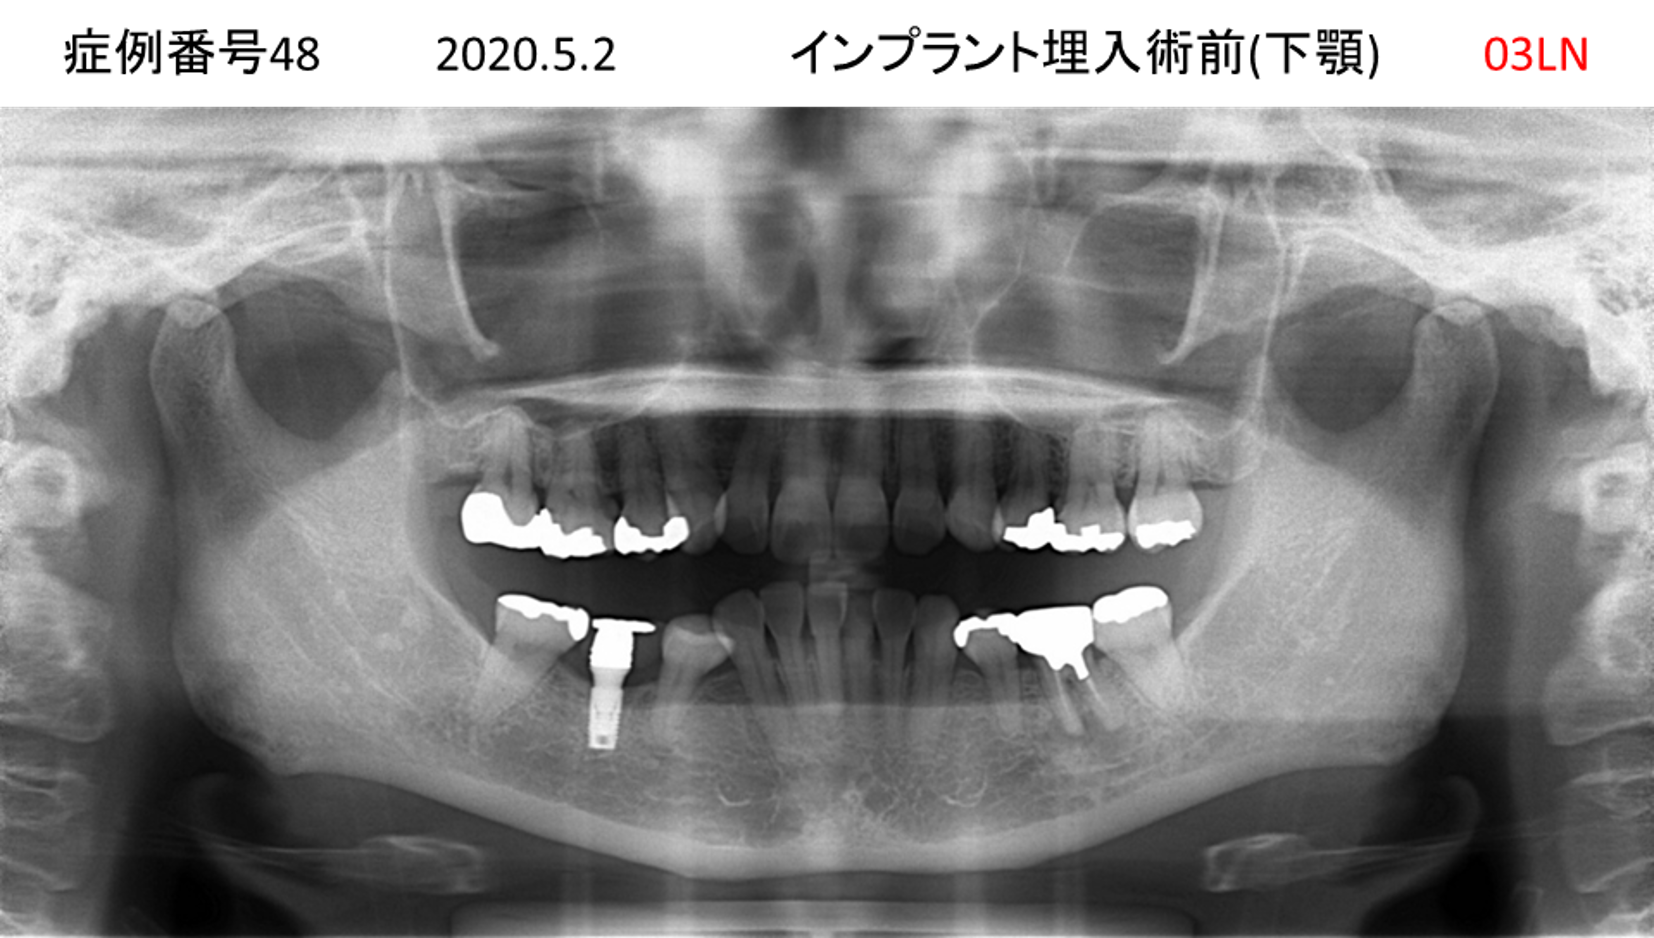

奥歯で噛めない患者様のインプラント症例

| 治療名称 |

インプラント |

| 治療費用 |

365万円+税 |

| 治療期間 |

5か月 |

| 患者さんの症状(主訴) |

奥歯で噛めない。上の前歯が揺れてきた。 |

| 治療内容 |

抜歯即時インプラント |

| 治療結果 |

食事に困らない。見た目がとても良くなった。 |

| 治療の注意点(リスク/副作用) |

インプラントが壊れたら再治療が必要 |